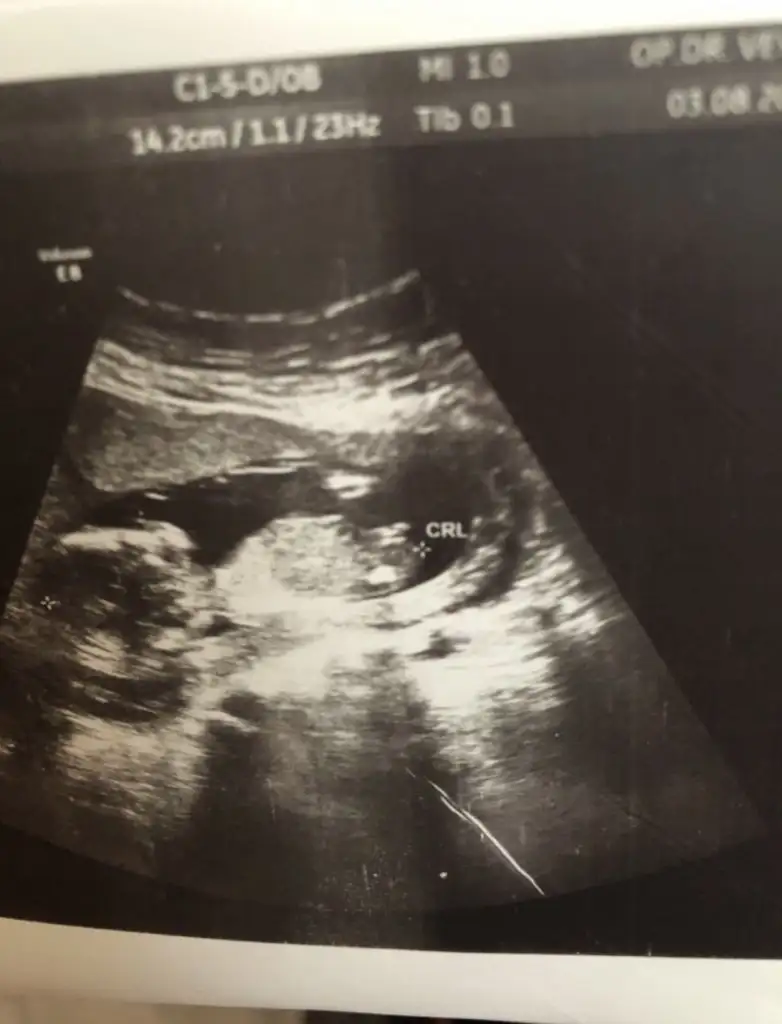

yaa kızlar bide benim bebişime baksanız,çok merak ediyorum.Bi oğlum var bide kız istiyorum.Ama hayırlısı tabi.

Eklentiler

• IMG_20190802_181427.webp

56,2 KB · Görüntüleme: 110